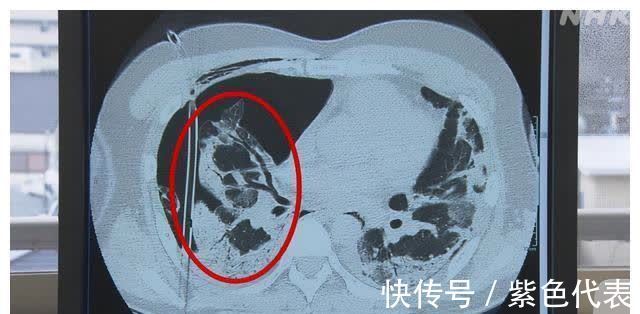

上面的图片是转院后对肺部的CT扫描影像。在CT影像中,正常情况下,肺部和血管等有组织的部分是白色的,什么都没有的地方是黑色的。而在患者的影像中,本该正常显示白色的地方是完全黑色的空洞。

因为新冠病毒将正常的肺组织破坏,变成了正常的三分之一大小。简直就像膨胀的气球开了一个洞,里面的空气好像漏了一样。